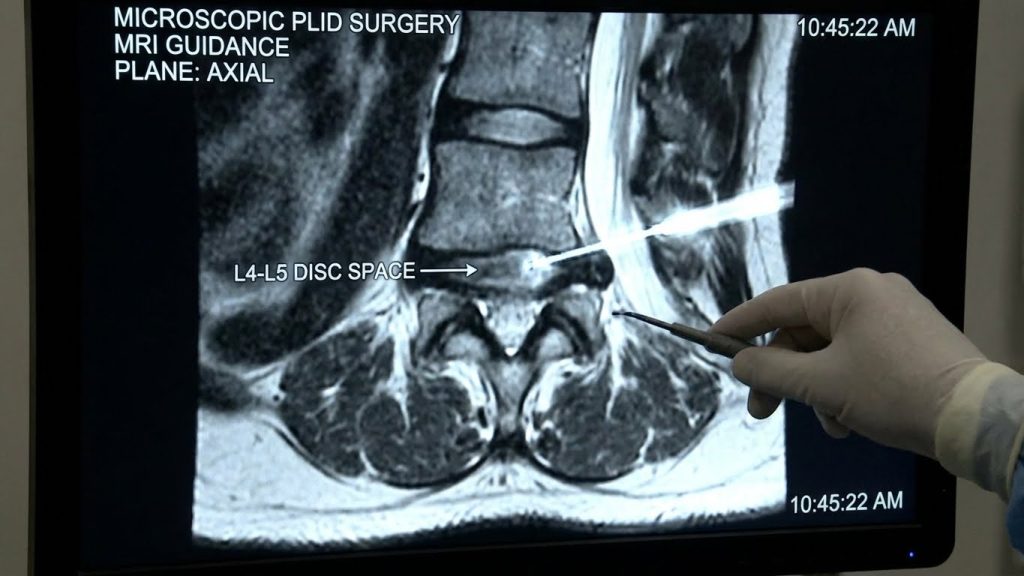

Microscopic PLID surgery is a modern, minimally invasive surgical procedure used to treat Prolapsed Lumbar Intervertebral Disc (PLID), commonly known as a slipped or herniated disc in the lower back. This technique uses a high-powered operating microscope to remove the damaged portion of the disc while preserving surrounding muscles, nerves, and spinal structures.

Microscopic PLID surgery, also called microdiscectomy, involves making a small incision in the lower back and using a surgical microscope to clearly visualize the affected nerve and disc. Only the herniated portion of the disc is removed, relieving nerve compression while maintaining spinal stability.